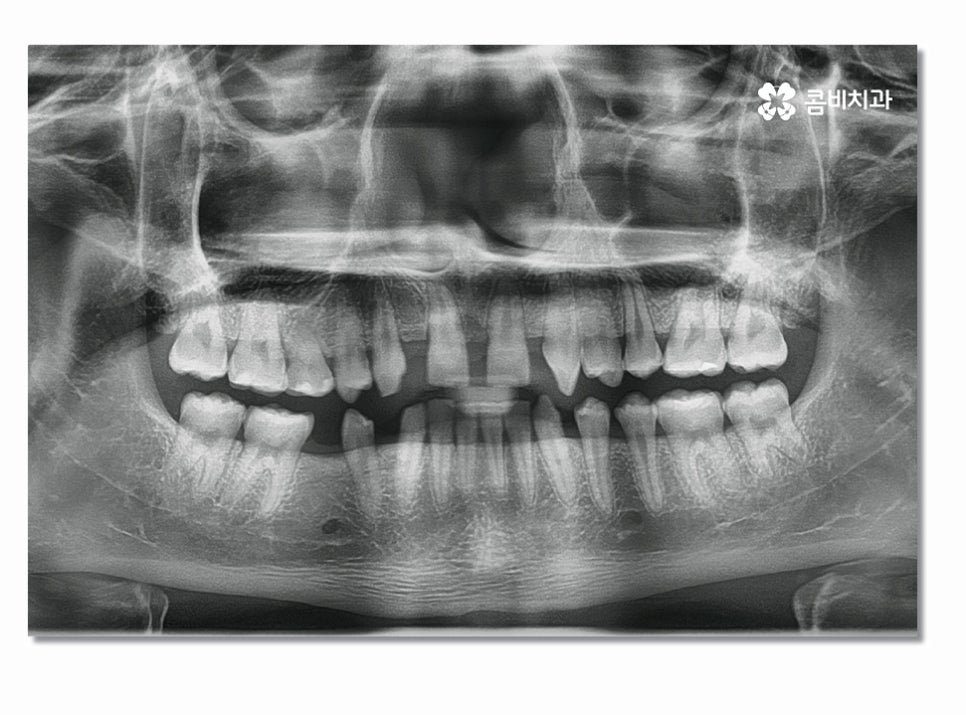

중년 이후에는 치주염이 심해져서 앞니임플란트 하게 되는 경우도

많지만 오늘 사례는 청결관리 미흡과 불규칙한 치열로

인해서 충치가 심해졌고 결국 발치 후 앞니 임플란트까지

하게 된 사례를 함께 살펴보실 거예요.

위 환자분의 경우에는 심미적으로 중요한 앞니를

잃기도 했지만 불규칙한 치열과 평소 청결관리 및 식습관의

문제가 있었고 비교적 젊은 나이에 영구치를

상실하고 이런 원인을 개선하기 위해

교정치료를 함께 병행한 케이스라고 할 수 있어요.